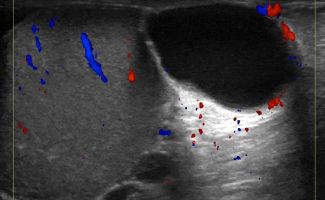

Η μελέτη με Έγχρωμο Doppler παρέχει κρίσιμες πληροφορίες σχετικά με την αγγείωση των όρχεων, ανιχνεύοντας αποκλεισμούς συστροφής ή φλεγμονές, όπως η ορχίτιδα.

Η δοκιμασία Valsalva σε συνδυασμό με το Έγχρωμο Doppler αποτελεί ένα από τα διαγνωστικά εργαλεία για την ανίχνευση της κιρσοκήλης, προσθέτοντας ένα επιπλέον επίπεδο ακρίβειας στη διάγνωση.